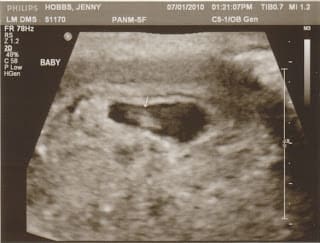

Jared, Mario and I are over the moon because we are expecting Baby Hobbs #2!!!

This was a big surprise for all of us. Here is how it went: